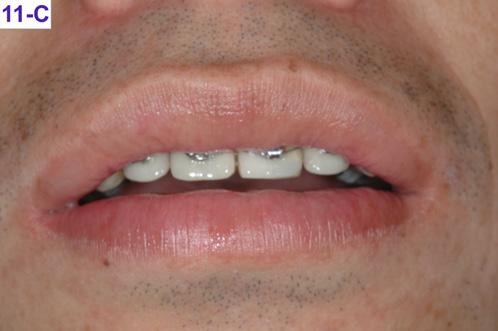

After re-bracketing, the treatment continued with the progression of the arch wires: a .014 NiTi, a .018 NiTi, a .019x025 “V” Force -3 and the final arch wire a .018x.025 SS. These final arch wires were left for three months. After this time, the esthetics, TMJ, airway, occlusion and alignment were evaluated. The patient reported that he was satisfied, and very happy with the result (Figure 11-A, B, C, D, E, F).9

FIG. 11C: Pre-de-bracketing, lips in repose

FIG. 11D: Pre-debracketing, posed smile